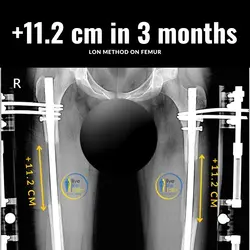

With the combined method (Lon method), an internal nail and an external fixation are attached which allow the bone to be extended from the outside.